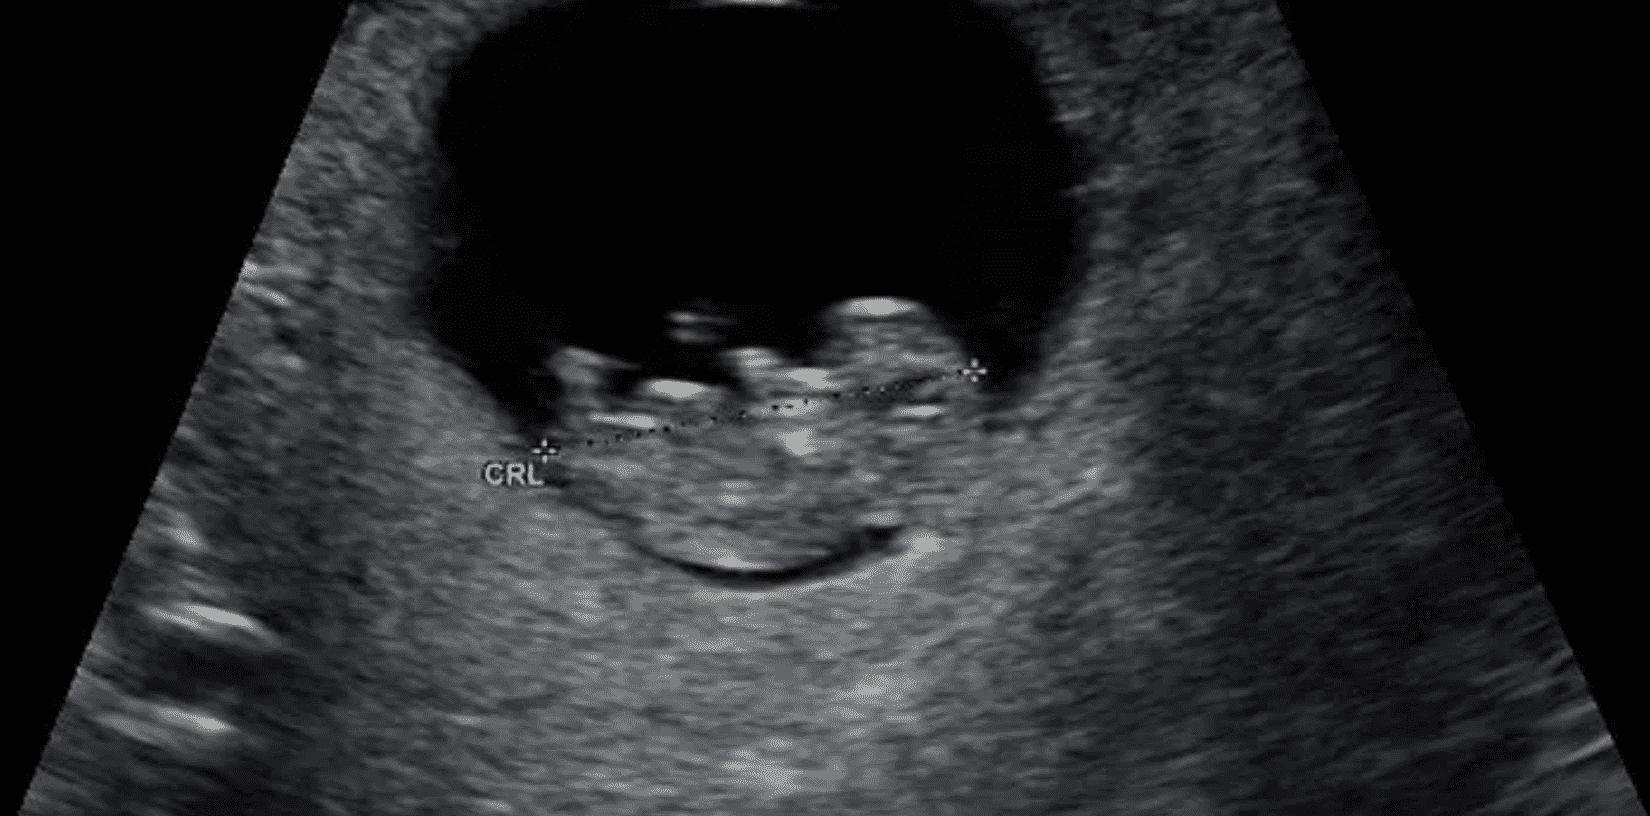

What happens at an Early Viability Scan?

Find out what happens at an early pregnancy scan appointment with this detailed guide!

The Ultimate Guide to Early Scans in Pregnancy

This guide explores what to expect during an Early Scan, when to book and what you can expect to see during the scan.